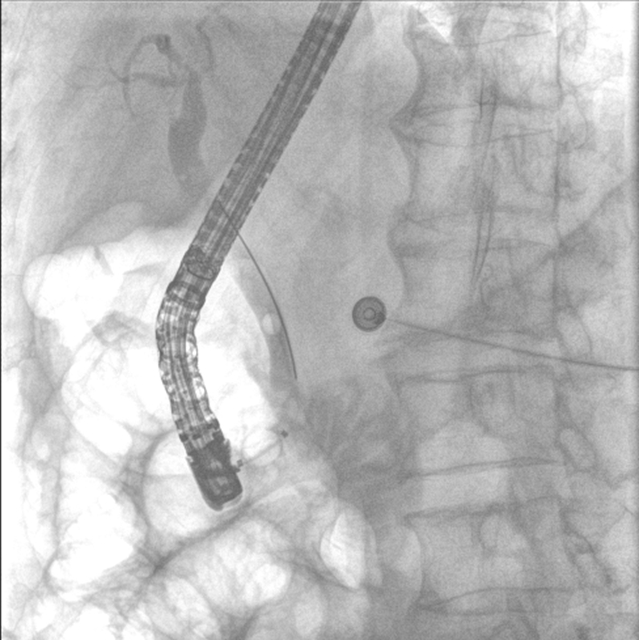

完善相关检查后,肝胆胰外科医生团队立即为张大爷实施了急诊内镜逆行胰胆管造影(ERCP)。

3.精准:“可视化”操作降低风险

内镜逆行胰胆管造影全程在X光和内镜直视下完成,医生能清晰看到结石位置、乳头形态,避免盲目操作。即使结石嵌顿严重(像"卡在墙缝里的石块"),也能通过球囊扩张或机械碎石取出,成功率高达90%以上。